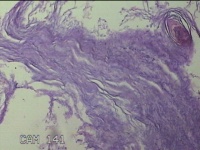

右耳道肿物

性别

女

年龄

30岁

临床诊断

耳内异物;外耳道肿物

一般病史

右耳堵塞感不适数年。

标本名称

大体所见

灰白粉红色不规则组织2.5x2x0.8cm一堆。

不具诊断价值。

角化物 结合临床排除胆脂瘤